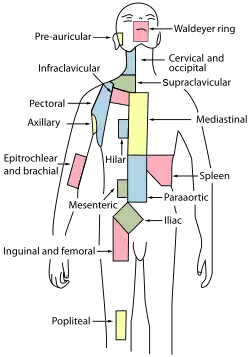

Murine inguinal lymph node beneath the bifurcation of superior epigastric vein. Bright structure visualised by MHC II-GFP construct, is the lymph node Lymph node regions

Lymph node regions